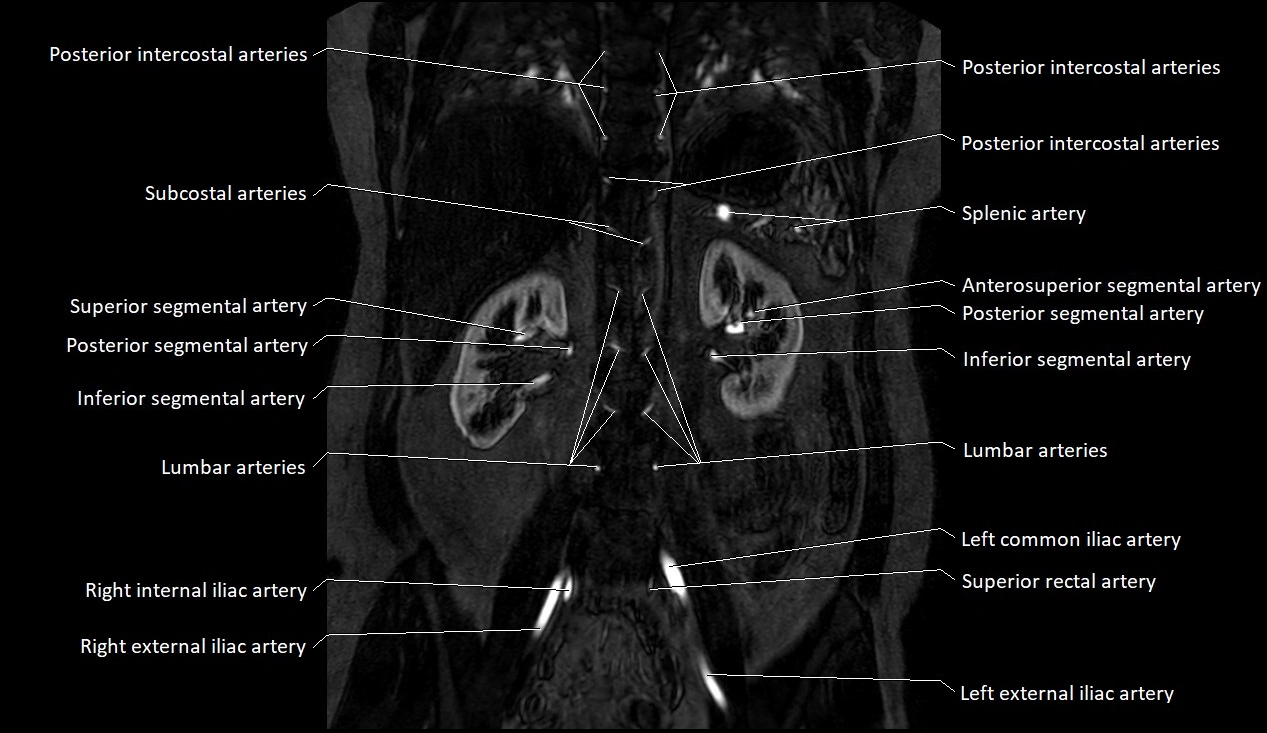

MRA (Magnetic Resonance Angiography):

• Contrast-enhanced MRA provides high-resolution imaging of the aorta and its branches

• Allows 3D reconstruction of visceral, parietal, and terminal branches

• Excellent for evaluating aneurysm size, dissection flap, stenosis, or preoperative planning

• Non-invasive alternative to conventional angiography